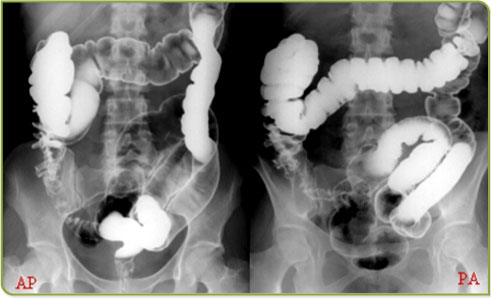

4. Clister opaco de duplo-contraste:  este exame radiológico é efectuado por injecção de uma solução de  bário, através do recto; em seguida, é bombeado ar para dentro do recto  (o bário e o ar melhoram as imagens do cólon e do recto.